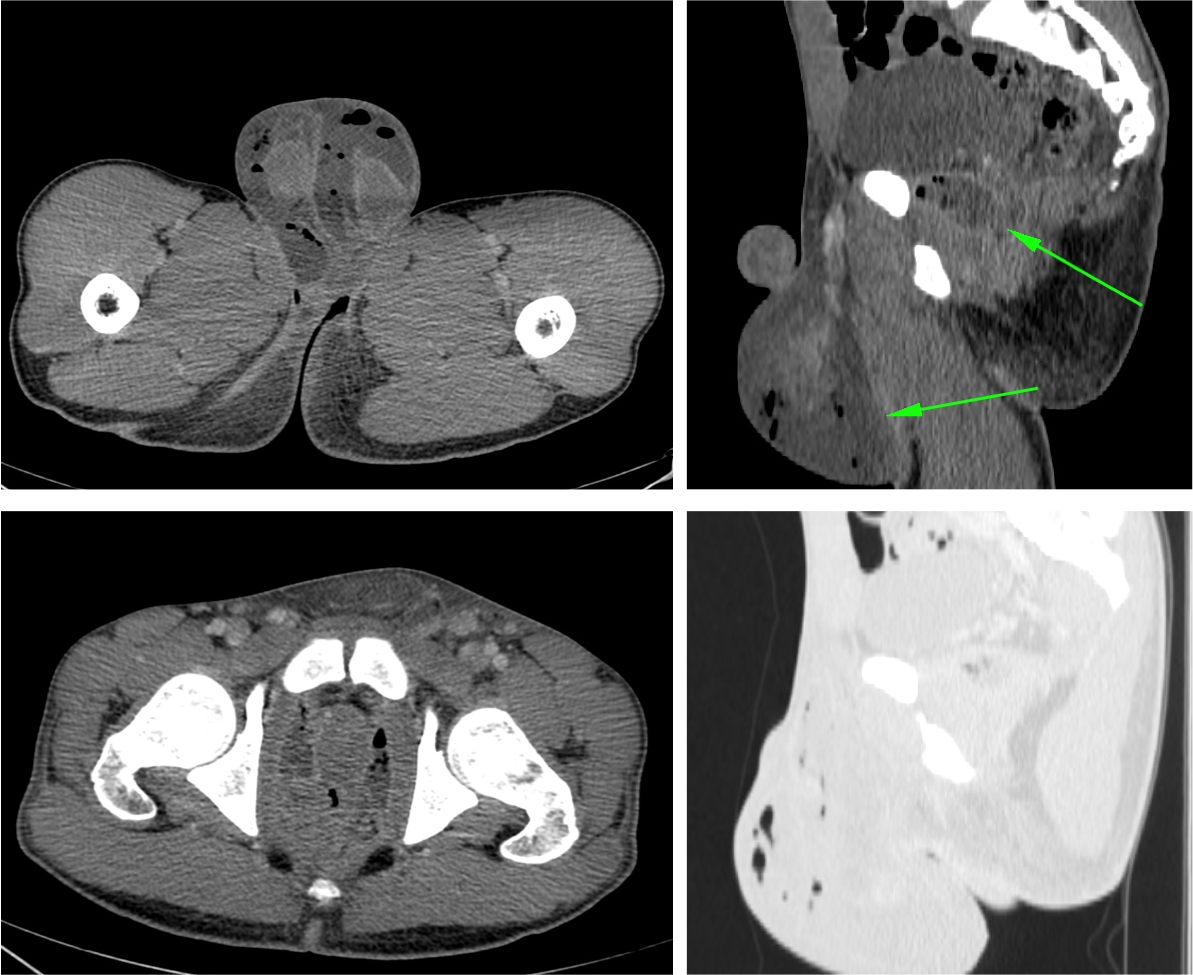

Tomografía Computarizada

Es la técnica que aprota mayor información, por ejemplo nos permite estudiar el retroperitoneo (se han publicado casos de Gangrena de Fournier por perforación de apéndice cecal). Define la causa, muestra el camino por el que se ha extendido el proceso y define las estructuras necrosadas,

- Engrosamiento de fascias e infiltración de partes blandas.

- Presencia de gas.

- Sirve para definir la extensión de proceso previa la cirugía.

- Permite identificar la etiologia del proceso (absceso perianal, fístula, hernias incarceradas, procesos retroperitonales, úlcera de partes blandas…).